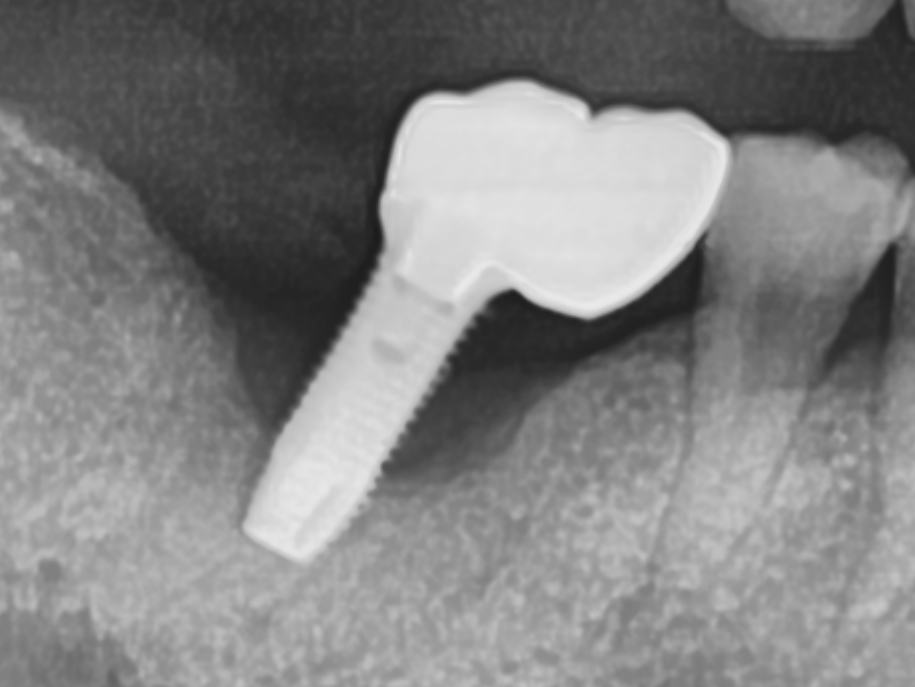

기존 임플란트 염증으로 임플란트제거, 골이식, 새 임플란트식립

치료전 2025.06.09 / 치료후 2025.09.15